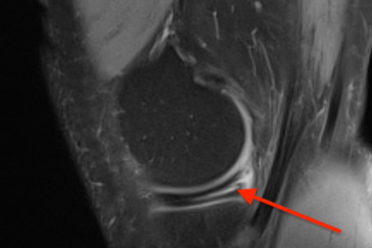

Czy kontuzja Roberta Lewandowskiego da się wyleczyć przed EURO? Kontuzje mięśniowe – naciągnięcia, naderwania i zerwania